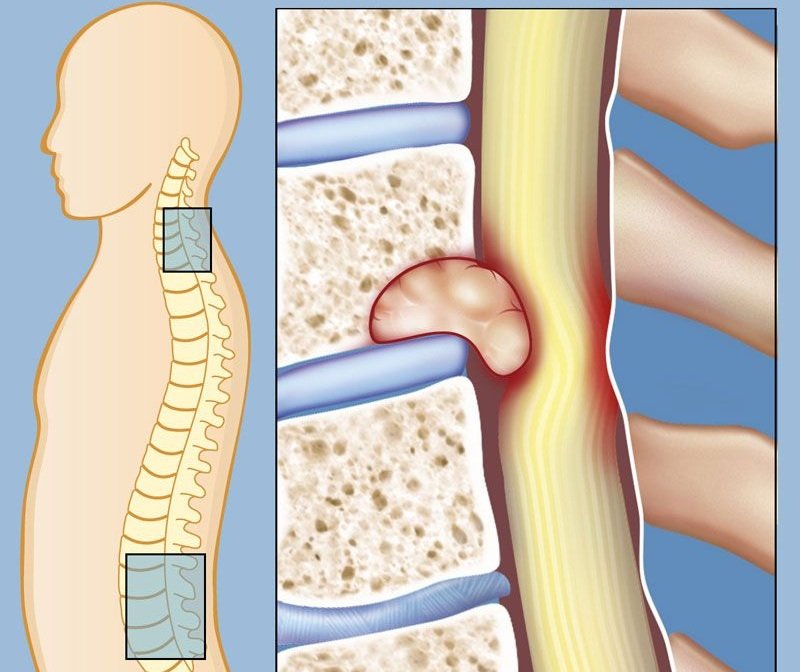

Когда метастазы в позвоночнике

Миграция мутировавших элементов и их оседание в структурах позвоночника – это непосредственная угроза для жизни онкобольного. В 80–90% случаев метастазирование множественное, а диагностирование довольно позднее.

Основным сигналом того, что атипичные клетки сформировали вторичные очаги, служит появление болевых импульсов. Как правило, их усиление наблюдается в ночные часы, при повышении физической нагрузки. После этого будут наблюдаться неврологические отклонения.

При отсутствии адекватной противоопухолевой терапии, у больного появляются:

- парестезии и параличи;

- онемение в конечностях;

- нарушение двигательной активности;

- затрудненность глотания, речи;

- иные нарушения в функционировании внутренних органов.

Выраженность и локализация вторичных расстройств напрямую определяется уровнем, куда проник в позвоночник метастаз.

Чтобы сказать, как скоро ожидать летального исхода в случае метастазирования в позвоночные структуры, специалист тщательно анализирует всю широту информации, полученной от лабораторных и инструментальных исследований. При своевременно проведенных лечебных процедурах, пятилетняя выживаемость достигает 65–70%.